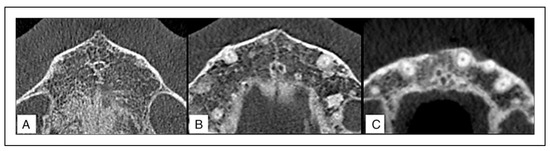

Nasopalatine Canal

A detailed analysis of the NPC revealed that it often commenced from 1 Stenson’s foramen in 87.9% of males and 69.2% of females, while from 2 foramina in 9.1% and 30.8% of males and females, respectively. Three foramina were found in 3.0% of males but none were observed in females (Figure 2). There was a statistically significant difference in the number of foramina with respect to gender (Chi-square test, P-value <.05).

Figure 2. Axial CBCT sections showing the number of Stenson’s foramina. (a) Single foramen (b) 2 foramina (c) 3 foramina.